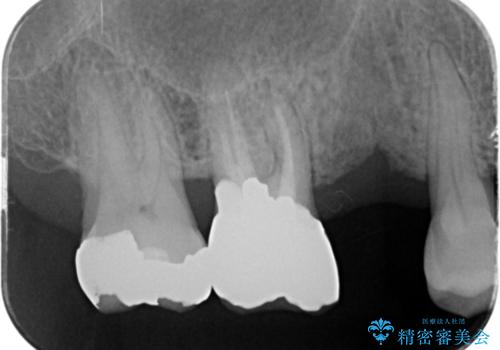

失った奥歯のインプラント治療

- 失ったままで放置していたインプラント治療を希望され来院されました。

抜歯後から十分に時間が経過しており、すぐにインプラントの埋入を計画できる状態です。